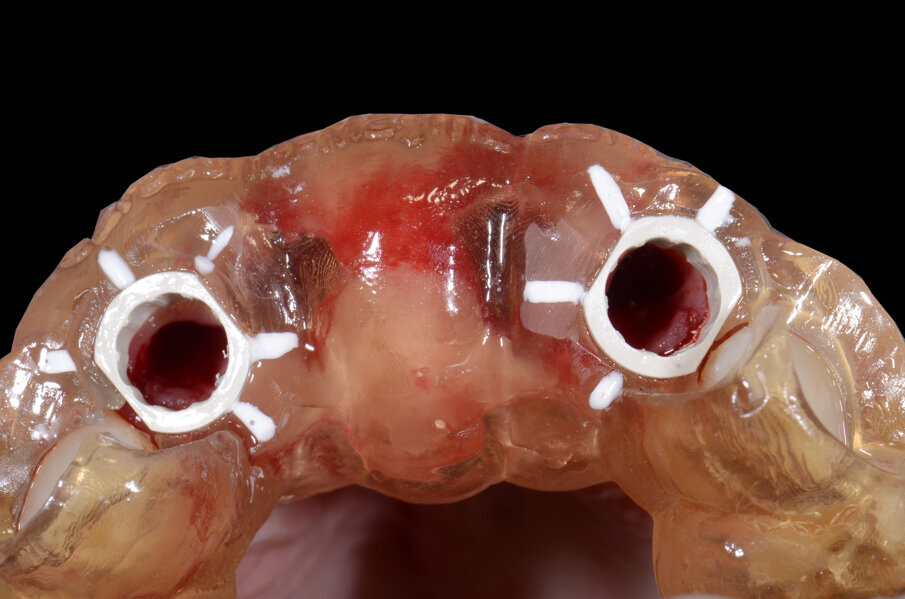

Il nostro obiettivo è quello di riuscire a dare alla paziente un provvisorio immediato nell’arco di due ore. Questo diventa possibile perché abbiamo utilizzato un flusso digitale fin dall’inizio. In laboratorio vengono realizzate la dima chirurgica (Figg. 16, 17), la dima protesica (Fig. 18) e anche il provvisorio (Figg. 19-21) che contiene delle alette di riposizionamento. Il tutto gestito con modelli digitali sui quali saremo in grado di funzionalizzare il provvisorio post-chirurgico (tecnica DIL). In un caso come questo se utilizziamo un flusso digitale possiamo evitare subito dopo la chirurgia di rilevare un’impronta degli impianti inseriti. Infatti, utilizziamo una dima chirurgica che ci faciliterà le fasi di intervento. La dima ci consentirà di non fare lembi e nessuna incisione di rilascio (Fig. 22), dopo aver inserito gli impianti (BLX Straumann) (Figg. 23-31) e aver controllato il loro alloggiamento, inseriamo sugli stessi dei transfert da impronta (Fig. 32).

Alloggiamo la dima protesica (Fig. 33), e blocchiamo i transfert con della resina trasparente (tecnica DIL) (Figg. 34, 35). In questo modo possiamo far riposare il paziente in studio dopo appena 35 minuti dall’inizio dell’intervento. La dima protesica, infatti (Fig. 36) con i transfert inseriti viene completata con l’unione degli analoghi ai transfert (Fig. 37). L’insieme così composto viene riadattato sul modello master digitale iniziale (Figg. 38-40) sul quale era stata costruita sia la dima chirurgica che la dima protesica come anche il provvisorio. Gli analoghi vengono bloccati sul modello con resina trasparente (Figg. 41-43). Alloggiamo il provvisorio sul modello master digitale così ottenuto (Figg. 44, 45).

Il piano di trattamento prevede l’estrazione degli elementi dentali, l’inserimento di due impianti e la realizzazione di una protesi fissa di quattro elementi. Il problema da gestire è quello della fase provvisoria. Non è ipotizzabile una protesi mobile e quindi programmiamo di inserire subito dopo l’intervento un provvisorio immediato. Questo ci consente di condizionare da subito i tessuti periimplantari e anche le zone dei ponti. Si rileva un’impronta digitale (Figg. 5, 6), e la programmazione degli impianti viene effettuata con un software di chirurgia guidata (Fig. 7) e la posizione degli impianti nello spazio biologico e nello spazio protesico viene fatta sulla base di una ceratura diagnostica (Figg. 8, 9). Inseriamo gli impianti virtuali nell’osso disponibile (Figg. 10-13) e in relazione all’aspetto protesico correggiamo l’asse di inclinazione degli impianti con componenti secondarie angolate a 17° (Figg. 14, 15). Questo ci consentirà di realizzare una protesi avvitata con i fori situati nella zona palatale.

Fig. 24 - Visione Occlusale.